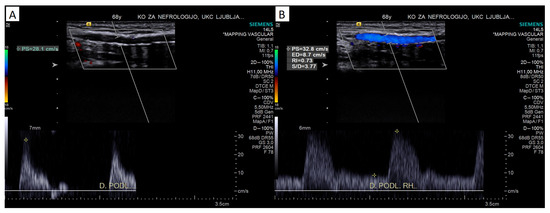

4.2.2. Pulsed-Wave Doppler Assessment

Peak Systolic Velocity

Doppler Curve Assessment, Acceleration Parameters

Reactive Hyperemia Test

5. Outcomes of AVFs Placed on Calcified Arteries